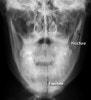

• The zygomatic arch fracture is more easily seen  on the OM30  (Occipito-Mental 30°) image.     • On the left (the non-injured side) overlying  structures give the impression of a fracture.  However, careful scrutiny shows the cortex is intact.

5) Tripod fracture

• 삼각골절이란 이름은 광대뼈의 이마돌기(frontal process), 광대활, 위턱돌기(maxillary process)를 침범하기 때문에 붙여진 것이다.   • 안면부 골절에서 가장 흔하다.   • 뺨의 충격이나 광대뼈의 직접 손상에 의해 발생한다.   • 진단은 Occipitomental 또는 Occipitomental 30º 영상에서 쉽게 진단되다.   • 연부조직의 부종, 공기액체층, 일부의 회전(rotation)이 관찰된다(CT에 가장 잘 관찰).

• 1 : The zygoma (asterisk) is separated from the  frontal bone at  the zygomatico-frontal suture   • 2 : Comminuted fracture of the zygomatic arch   • 3 : Orbital floor fracture   • 4 : Breach of the lateral wall of the maxillary  antrum

• A 'tripod' fracture has 4 visible components -  not always all visible.   • 1 : Orbital floor fracture   • 2 : Fracture of the lateral wall of the maxillary  antrum    • 3 : Zygomatic arch fracture of the maxillary  antrum is due to it filling with blood.  • 4 : Widening of the zygomatico-frontal suture  Increased density of the maxillary antrum is due  to it filling with blood.

• A fluid level of blood seen in the maxillary antrum  may be the only obvious sign of fracture   • A : Widened zygomatico-frontal suture   • B : Zygomatic arch fracture   • C : Orbital floor fracture   • D : Lateral maxillary antrum wall fracture